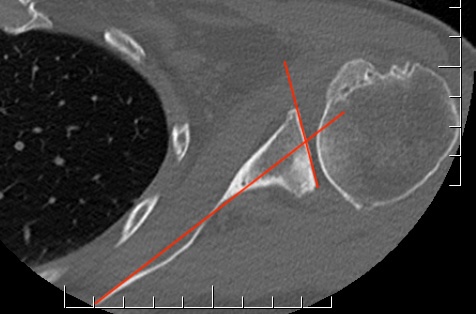

Glenoid version measurement

1. Xray v CT

- glenoid version axillary xray v CT

- glenoid retroversion overestimated on xray in 86%

- mean difference in measurements between xray and CT was 6.5o

2. Include scapula

Chalmers et al. J Should Elbow Surg 2017

- 14 B2 glenoids

- glenoid version measurement accurate if > 50% of the scapula width included

3. Measurement techniques

a. Friedman method

- tip of the medial border of the scapula to the midpoint of the glenoid fossa

b. Scapula body method

- intersection of the scapula body axis and the glenoid surface

- 3o difference in measurement of glenoid version between the two

- excellent reliability for both measurement techniques

c. Glenoid vault method

- tip of scapula vault to centre of glenoid